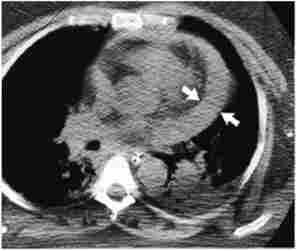

Комп'ютерна томографія. Регулярне використання комп'ютерної томографії (рис. 25.1) для оцінки органів черевної та грудної порожнин спочатку не застосовувалося при травмах, так як для виконання цього виду дослідження були потрібні певні умови: стабільна гемодинаміка пацієнта, транспортування його в спеціально обладнаний кабінет, наявність рентгенолога для розшифровки отриманих знімків , тривалість проведення дослідження та ін. в даний час тривалість сканування при комп'ютерної томографії значно скорочена у зв'язку з використанням з іральних томографів, і метод став визнаною частиною арсеналу діагностики ушкоджень. Точність комп'ютерної томографії у гемодинамічно стабільних пацієнтів з закритими травмами досягає 92-98%.

Мал. 25.1. Комп'ютерна томографія грудної клітини.

Стрілками вказана тампонада перикарда (скупчення крові в перикарді)